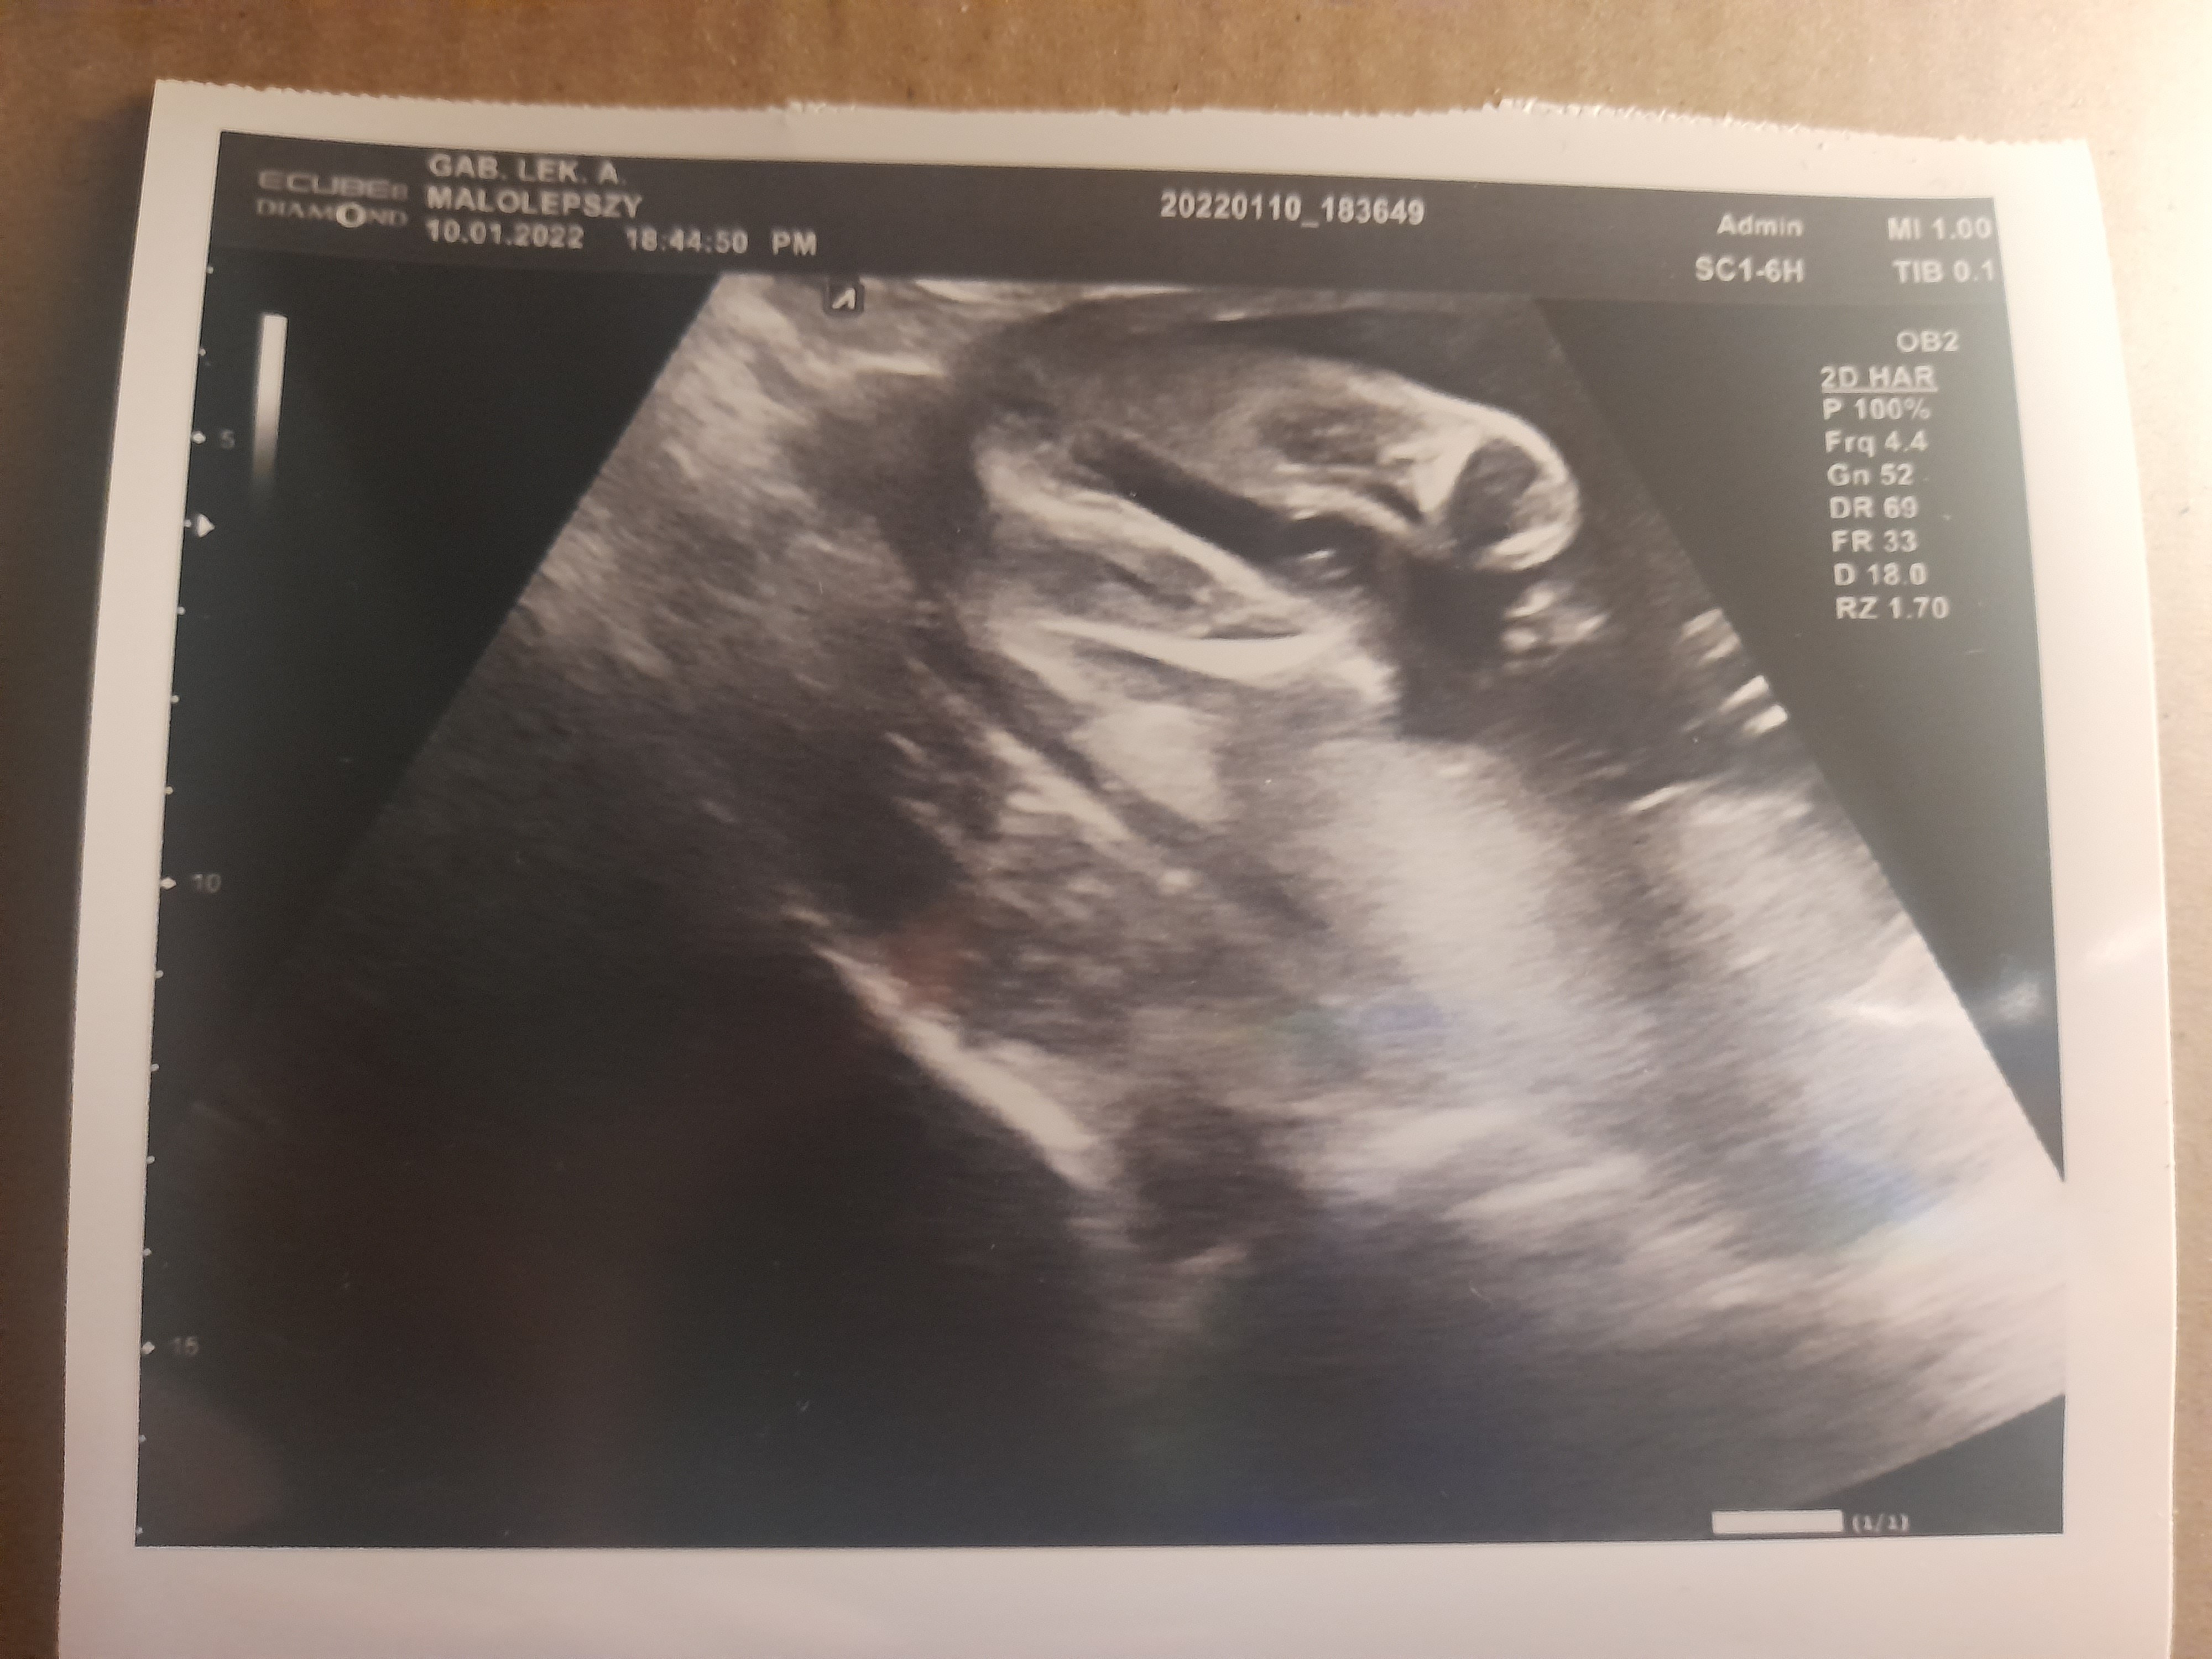

Dziewczynka czy nie!!!

Witam mi sie wydaje że dziewczynka ale nie jestem pewna. Może ktoś będzie lepiej widzial. Proszę o podowiedź